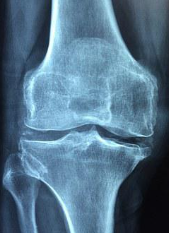

통풍은 인체 내 결정체의 증가로 인해 발생하는 만성적인 질환입니다. 이 질환은 혈액 내부의 요산 농도가 높아져 결정체가 형성되어 발생합니다. 흔히 발목, 발가락, 손가락, 무릎 등의 관절에서 발생하며 갑작스럽게 발생하는 통증과 함께 염증 및 부종이 동반됩니다. 이번 글에서는 통풍의 대표적인 증상인 통증, 염증 및 발진 등에 대해 상세히 알아보겠습니다.

통풍의 가장 대표적인 증상은 갑작스럽게 발생하는 관절 통증입니다. 발작적인 통증으로 시작하여 몇 시간에서 몇 일간 지속될 수 있으며, 빈번한 발작으로 인해 관절에 손상을 줄 수 있습니다. 발작적인 통증은 보통 밤 늦은 시간에 시작하여, 손가락, 발가락, 발목, 무릎 등의 관절에서 발생합니다. 이러한 통증은 불규칙적으로 발생할 수 있으며, 발작이 진행될 때 통증의 강도는 증가됩니다.

통풍은 염증을 동반합니다. 염증은 관절 주위의 부위에서 발생하며, 염증이 있는 부위는 붉게 부어오르고 따끔거리는 통증이 동반됩니다. 염증이 심한 경우 관절이 뻣뻣해지고 움직이기 힘들어집니다. 또한 염증은 주변 조직에 압력을 가해 근육 통증을 유발할 수도 있습니다. 이러한 염증은 일반적으로 통증이 발생하는 부위와 함께 발생합니다.